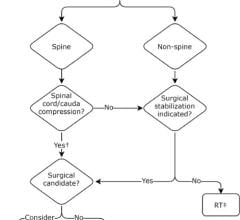

The 602 patients who agreed to take part in the ‘RAPID’ trial had a PET scan performed after their chemotherapy. Patients who tested positive received radiotherapy. Those who tested negative were divided into two groups – one group of 211 patients received no further treatment, while the other group of 209 had the standard radiotherapy.

After three years of regular check-ups, the proportion of patients who were alive and free of disease was 94.6 percent in the radiotherapy group, and 90.8 percent in the group which hadn’t received further treatment.

Lead researcher, Professor John Radford, is based at The University of Manchester’s Institute of Cancer Sciences and the Christie NHS Foundation Trust. He said: “This research is an important step forward. The results of RAPID show that in early stage Hodgkin lymphoma radiotherapy after initial chemotherapy marginally reduces the recurrence rate, but this is bought at the expense of exposing to radiation all patients with negative PET findings, most of whom are already cured.”